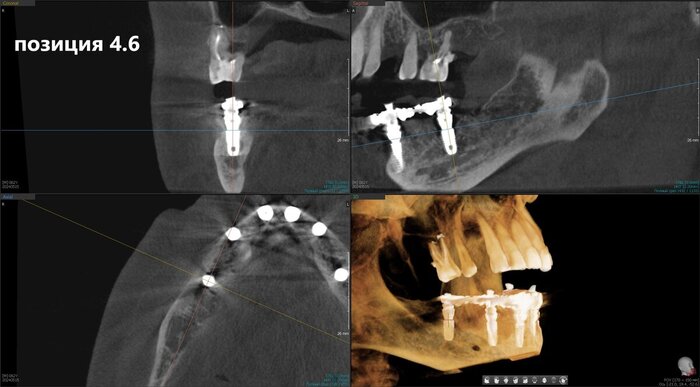

Имплантаты установлены и пациент отправляется на КЛКТ. Каждый раз очень радуется имплантолог, что аппарат находится в клинике. Я тоже рада)

Позиция 4.6

Имплантолог видит, сколько мм можно докрутить безопасно для структур челюсти (нервов, сосудов). Делает дело.